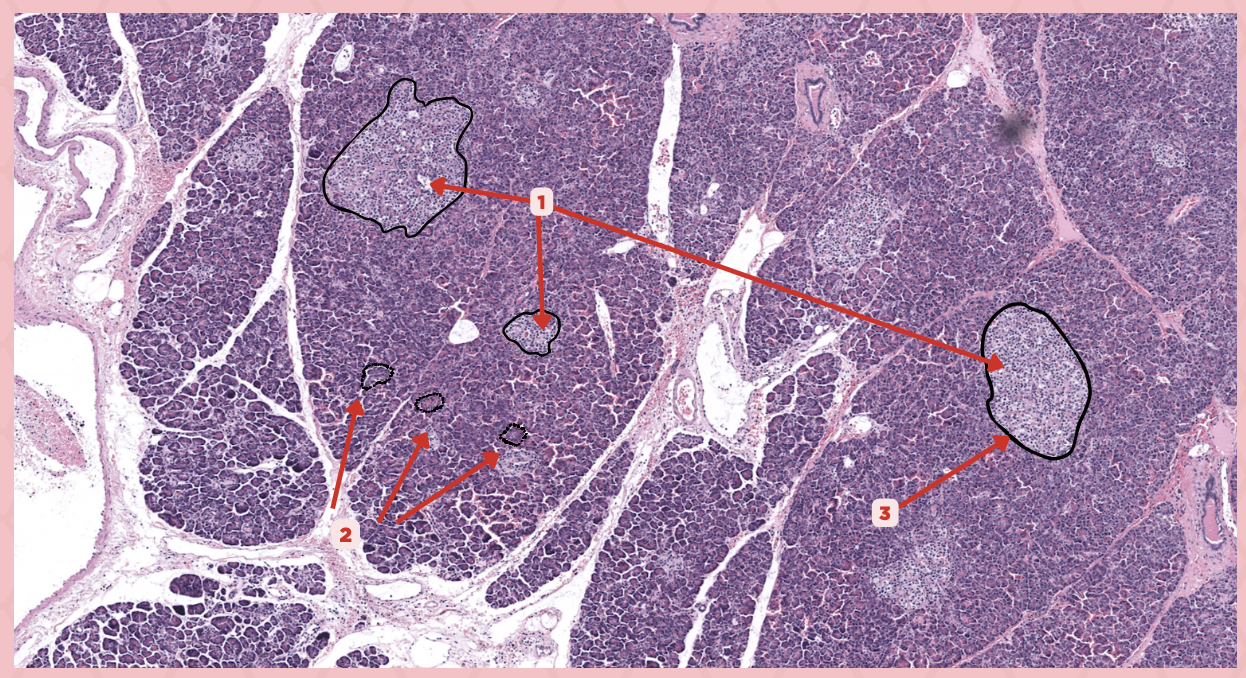

Pancreas

Identify the specimen.

Islets of Langerhans

Identify the structure labeled as 1.

Pancreatic Acini

Identify the structure labeled as 2.

Reticular Tissue

Identify the structure labeled as 3.

Beta-cells

Which cells occupy the central area of #1?

Pancreatic Acini

#3 delineates the pale- staining cells from the darker-staining cells. What do you call the darker-staining cells?